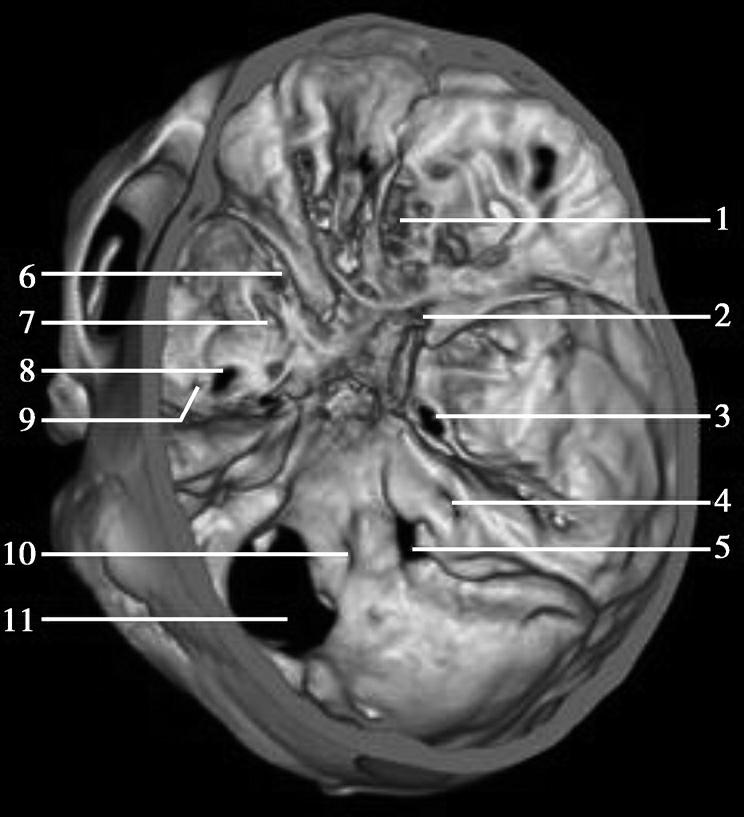

CT血管成像(CT angiography,CTA及CT venography,CTV)通过三维重建技术可显示颅内动静脉的走行、血管壁及血管周围等情况(图1-2-73~图1-2-75)。

图1-2-73 正常颅脑CTA

1.大脑前动脉;2.大脑中动脉;3.颈内动脉;4.大脑后动脉;5.基底动脉;6.椎动脉